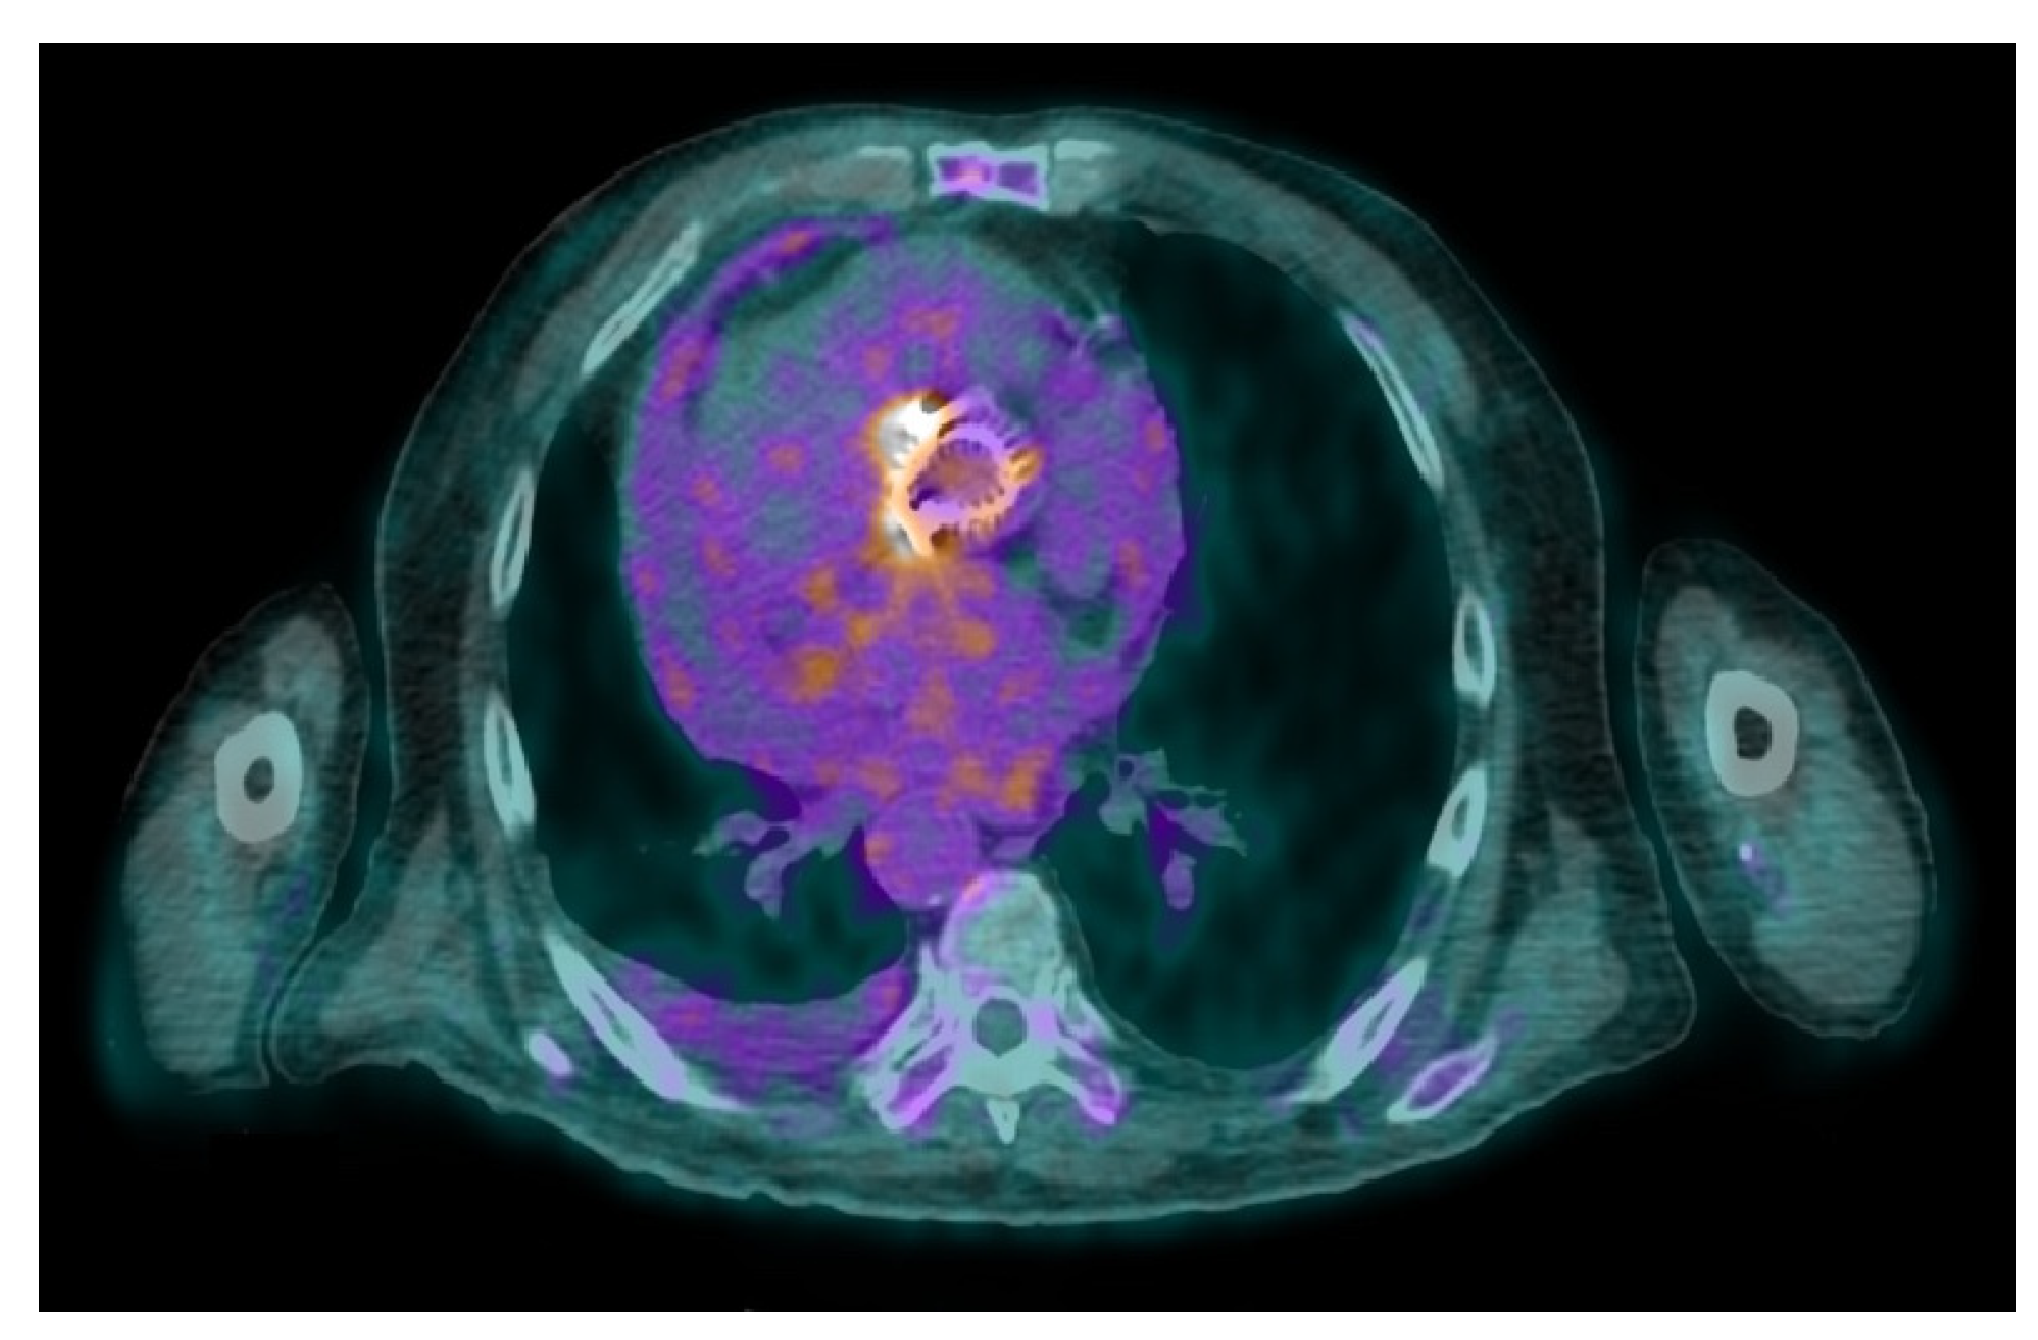

- Uncovering hidden infectious spread: FDG-PET/CT can also detect clinically silent disseminated infectious disease, identifying primary infection source, and/or septic embolism, which can be crucial for diagnosis and guiding patient management.